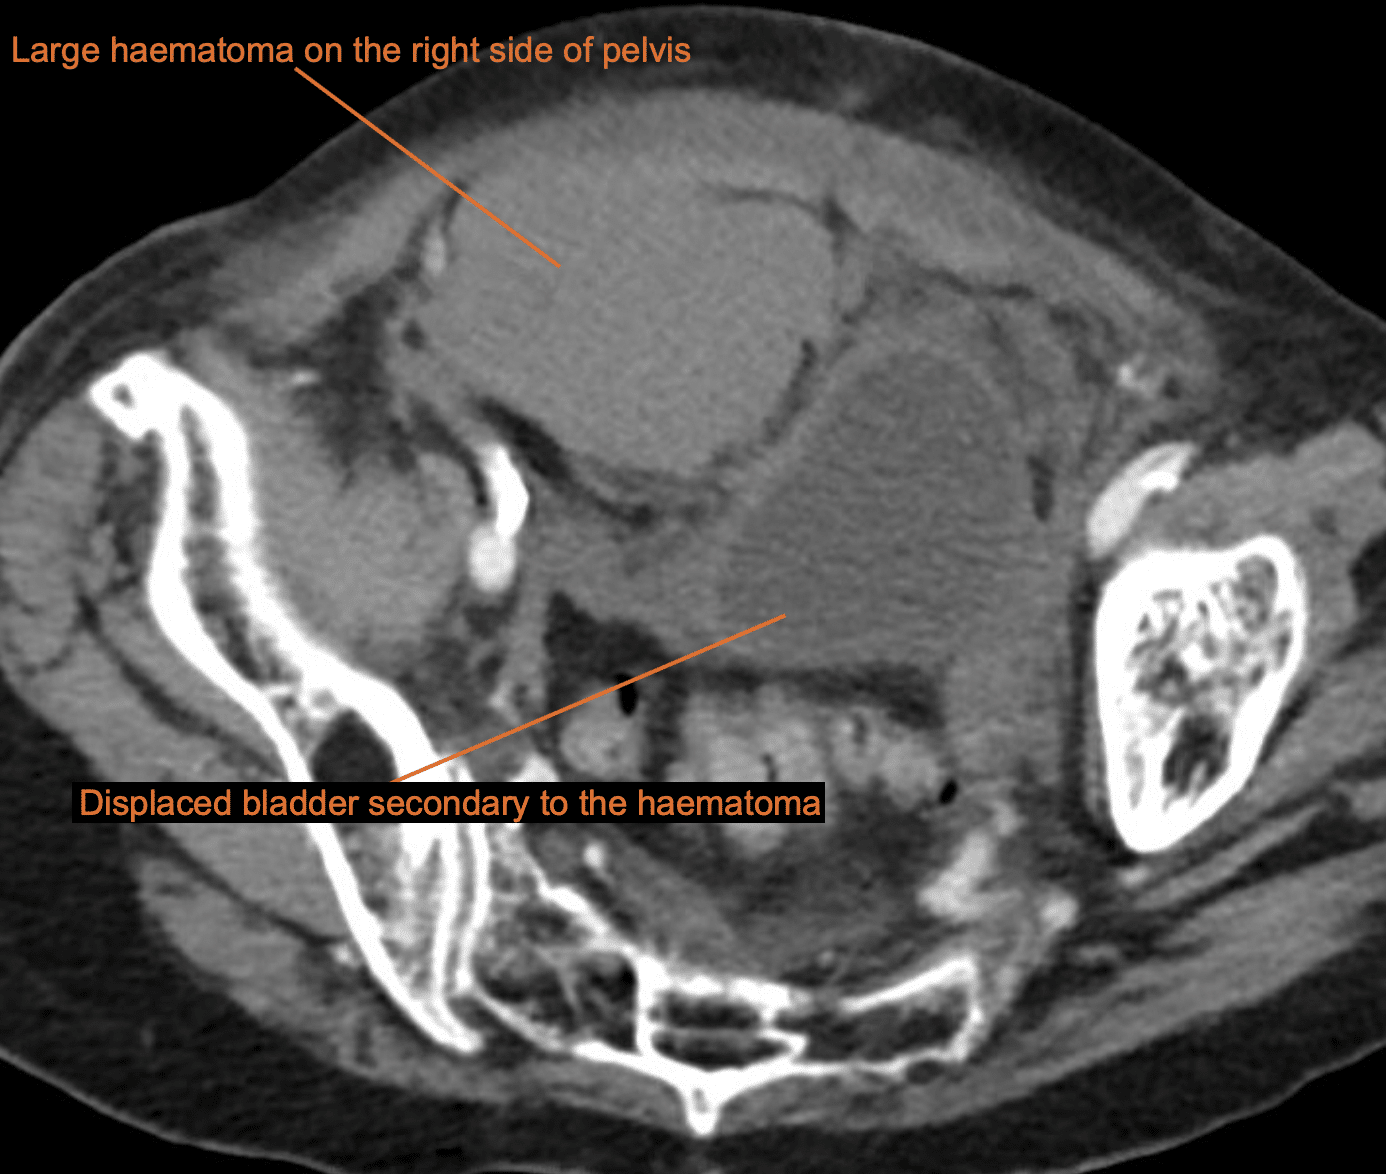

Several hours later, while awaiting admission to the ward, this patient becomes haemodynamically unstable and describes worsening lower pelvic pain.

She is sent for CT scan of the abdomen and pelvis.

Describe and interpret the CT scan